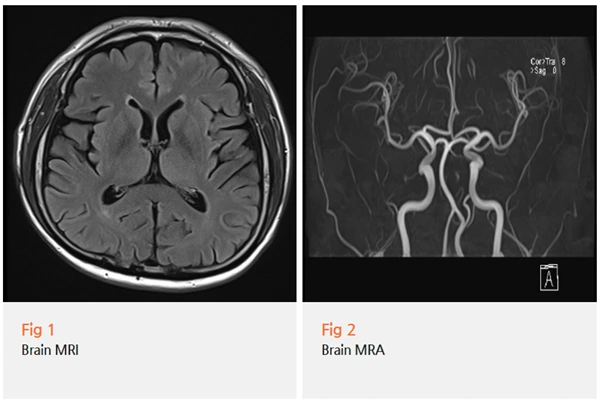

그런데 저는 거기서 멈추지 않았어요.

당일 목 MRI도 함께 확인했죠.

목 MRI를 자세히 보니, 목 디스크와 경추 협착이 발견됐어요.

%EA%B7%B8%EB%A6%BC3.png?type=w966

환자분께 설명해드렸죠.

귀 통증의 원인이 목에서 나오는 신경 때문일 수 있다고요.

목 뒤쪽에서 나오는 '후두부신경'과 '대이개신경'이라는 신경이 있는데,

이 신경들이 귀 뒤쪽과 귀 주변까지 연결되어 있다고요.

목 디스크나 협착 때문에 이 신경들이 자극을 받으면,

실제로는 목이 문제인데 귀가 아프게 느껴지는 거예요.

이걸 '연관통'이라고 해요.